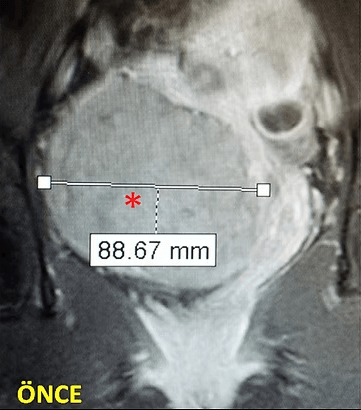

29 yaşında, adet uzaması, kansızlık ve sık idrara çıkma şikayetleri olan ve daha önce 2 kez miyomektomi olan hasta. Emar’da idrar kesesine bası yapan 85mm çaplı miyom (*) mevcut. Embolizasyondan sonra miyomun öldüğü ve küçüldüğü izleniyor. 7 ay sonra hasta şikayeti kalmamış ve 4 yıllık takip süresince yeni miyom oluşmamıştır.